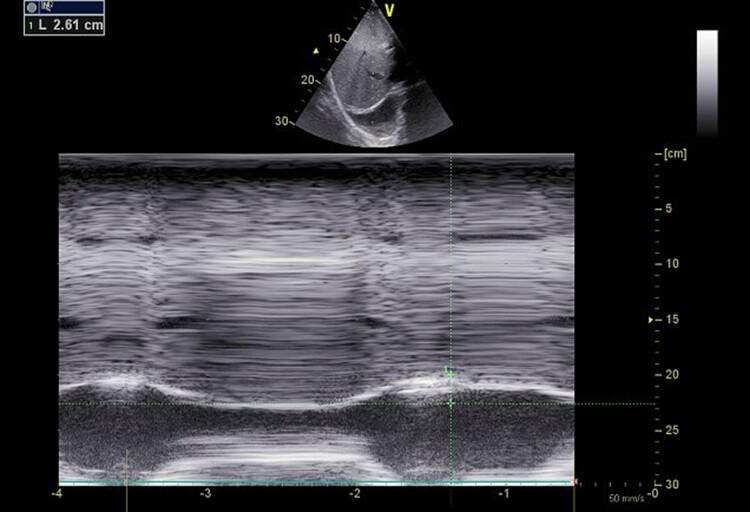

急性心力衰竭中的膈肌超声与膈肌二维斑点追踪成像:病例系列

Diaphragm ultrasound and diaphragmatic 2D speckle tracking imaging in acute heart failure: a case series.

Respiratory muscle function can be affected in patients with heart failure. Ultrasound can be used to assess diaphragm, the main inspiratory muscle. Speckle tracking imaging is an imaging technology providing the evaluation of tissue deformation during contraction. We aimed to evaluate the contribution of traditional echography and 2D speckle tracking imaging in the evaluation and monitoring of patients with acute heart failure (AHF).

CASE SUMMARY

We report a series of four cases of AHF. Diaphragm ultrasound coupled with diaphragm 2D speckle tracking imaging was performed at admission and after decongestive therapy, in cardiac intensive care unit. Patients, at admission, disclosed higher diaphragm 2D strain value and higher diaphragm inspiratory motion value in the context of higher cardiac loading that significantly decrease after decongestive therapy, except for one patient. Diaphragm motion remained less than 10 mm (weakness), despite medical therapy in Cases 2, 3, and 4. Among them, 3 months later, one patient (Case 3) experienced an episode of AHF.

心力衰竭患者的呼吸肌功能可能会受到影响。超声可用于评估主要吸气肌膈肌。斑点追踪成像技术是一种可在组织收缩时评估其变形情况的成像技术。我们旨在评估传统超声心动图和二维斑点追踪成像在急性心力衰竭(AHF)患者评估和监测中的作用。

病例总结

我们报告了4例AHF病例。在心脏重症监护病房,入院时和进行充血性心力衰竭治疗后均进行了膈肌超声检查及膈肌二维斑点追踪成像。患者入院时,在心脏负荷较高的情况下,膈肌二维应变值和膈肌吸气运动值较高,除1例患者外,充血性心力衰竭治疗后这些值显著降低。在病例2、3和4中,尽管进行了药物治疗,但膈肌运动仍小于10毫米(无力)。其中,3个月后,1例患者(病例3)发生了一次AHF发作。